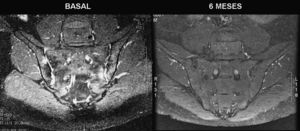

En otro estudio3, se realizó una RM basal a 13 pacientes con espondilitis anquilosante, puntuando los hallazgos con el sistema ASSpiMRI-a. Tras 6 meses de tratamiento con adalimumab se repitió la RM. Todos los pacientes mostraron mejora en las puntuaciones del ASSpiMRI-a y de las imágenes inflamatorias en articulaciones sacroilíacas (fig. 2).

PronósticoComo hemos visto hasta ahora, la RM ha mostrado ser particularmente útil para demostrar la presencia de sacroileítis precoz y puede predecir el desarrollo de cambios radiográficos y de sacroileítis significativa con 2-3 años de adelanto con respecto a las radiografías23. Esto indica que la RM podría utilizarse para el diagnóstico precoz, antes de desarrollar cambios radiográficos, y posiblemente se incluya en futuros criterios de clasificación de las espondiloartritis. No obstante, la relación coste/eficacia de esta técnica aún no se ha valorado en este contexto24.